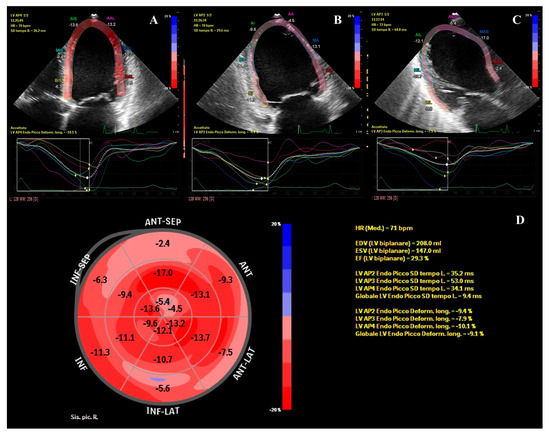

- We presented a case of new onset dilated cardiomyopathy (DCM) with renal infarction in a young man on a treatment with high-dose isotretinoin.

- Possible known causes of DCM using a complete cardiac imaging assessment, genetic testing, and laboratory analysis have been ruled out.